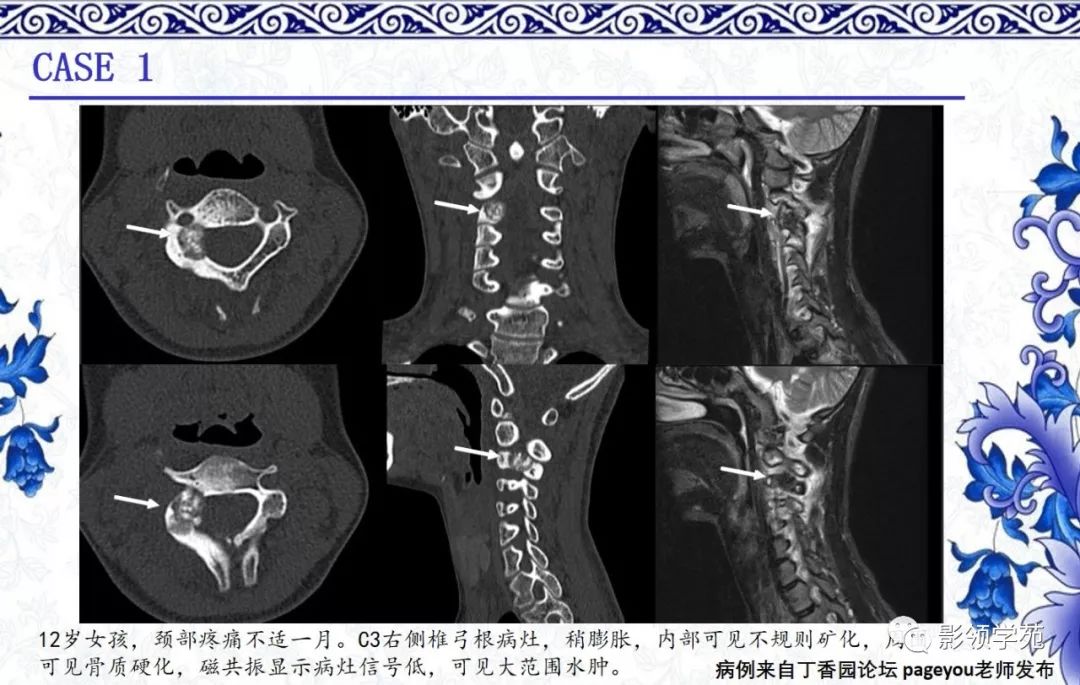

经典病例丨骨肿瘤疑难病例讨论二

图片尺寸600x729